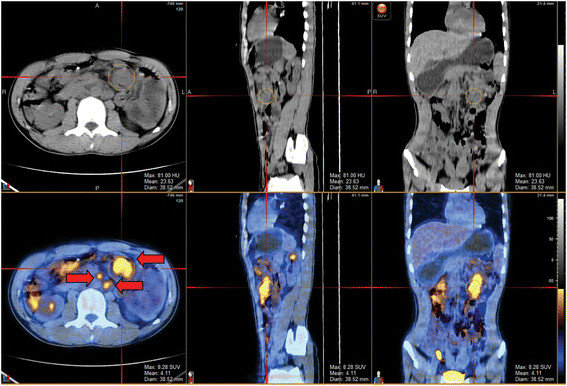

A CT scan has the benefit of being able to provide the clinical team with far more detail than an ordinary x-ray. The areas of concern will normally show up as masses that have appeared since the previous scan. The scans are indicative of a change in the body and the likelihood of a return of the cancer. However, a PET CT scan can provide yet more information and act as a positive confirmation.

A PET-CT scan (Positron Emission Tomography–Computed Tomography) is a powerful imaging test that combines two different technologies—a PET scan and a CT scan—into one procedure. Together, they provide both metabolic (how tissues are working) and anatomical (how tissues look) information about your body.

The computer combines the PET and CT images so doctors can see exactly where abnormal activity is happening. For example, a bright spot (high FDG uptake) on PET might correspond to a mass seen on CT—suggesting a tumour or inflammation. Radiologists and oncologists then review these images to assess: